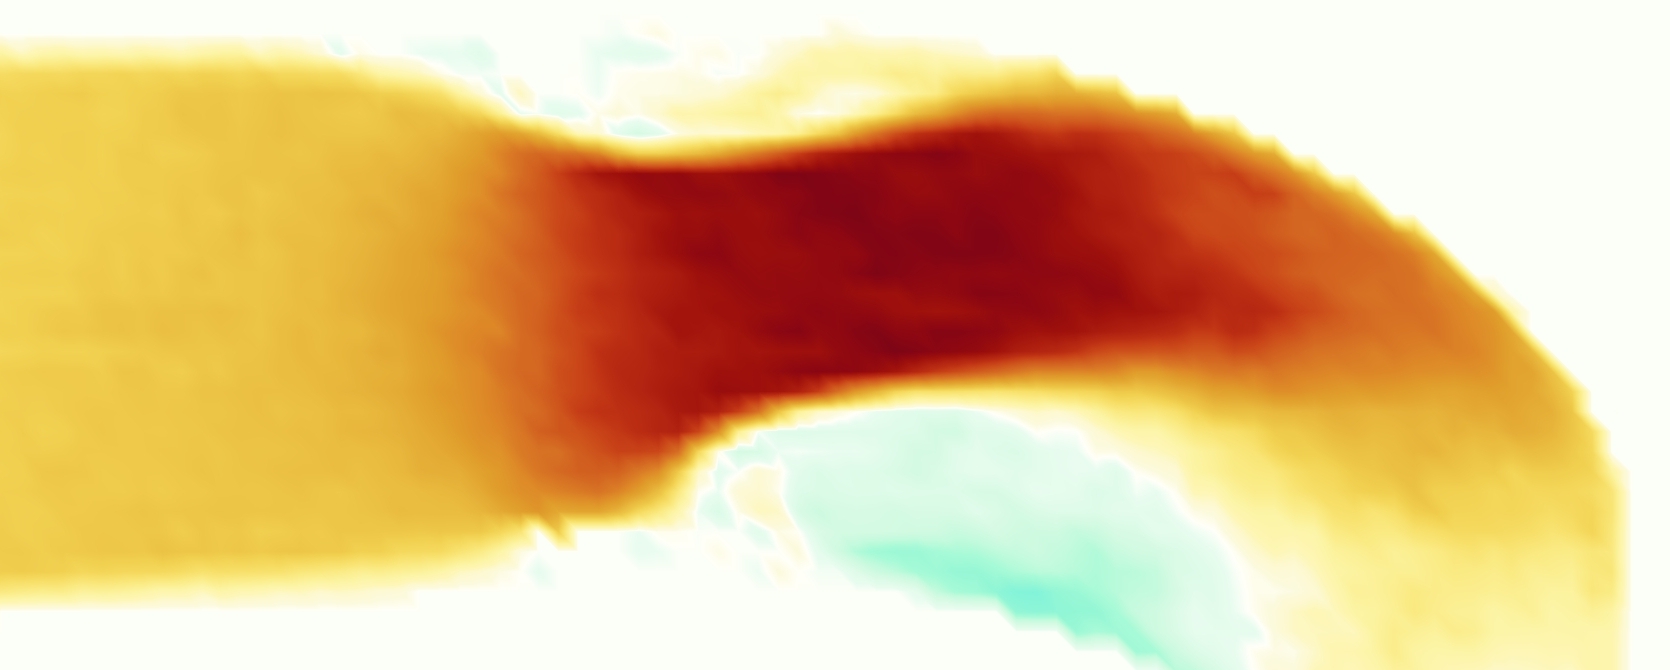

The emergent hemodynamics showed excellent qualitative agreement with experiments. Slice views of the axial component of fluid velocity ( component) in the sagittal plane that cuts through the center of the vessel, parallel to the flow direction, are shown in Figure 5. The flow in both the simulation and the experiment began to accelerate at the same time, with a jet forming through the open valve leaflets. The velocity, angle, and shape of the jet agreed well between the two cases during systole. The simulation captured the slight upward angle of the jet, which was not fully centered in the vessel. It also matched the location where the jet impacts the wall and the slower speed of the jet as it turns with the MPA downstream. As the flow decelerated, the fluid along the interior curve of the vessel reversed first while forward flow persisted where the jet was strongest, as seen in both the simulation and experimental results.

In both the experiment and the simulation, a separation region of reverse flow developed along the interior curve of the vessel under the core jet through the valve. The reverse flow began to develop at the same time in the cardiac cycle and grows throughout systole. The simulation lacked reversed flow in the entire region where reversed flow was present in the experiment, but this region developed some flow separation and had much slower flow than elsewhere in the vessel. Thus, the simulation captured that this is a distinct region from the core jet through the valve opening. There was a smaller amount of slower and slightly reversed flow along the outer curve of the vessel, close to the valve annulus and scaffold support. This region was well-matched between the experiment and the simulation.